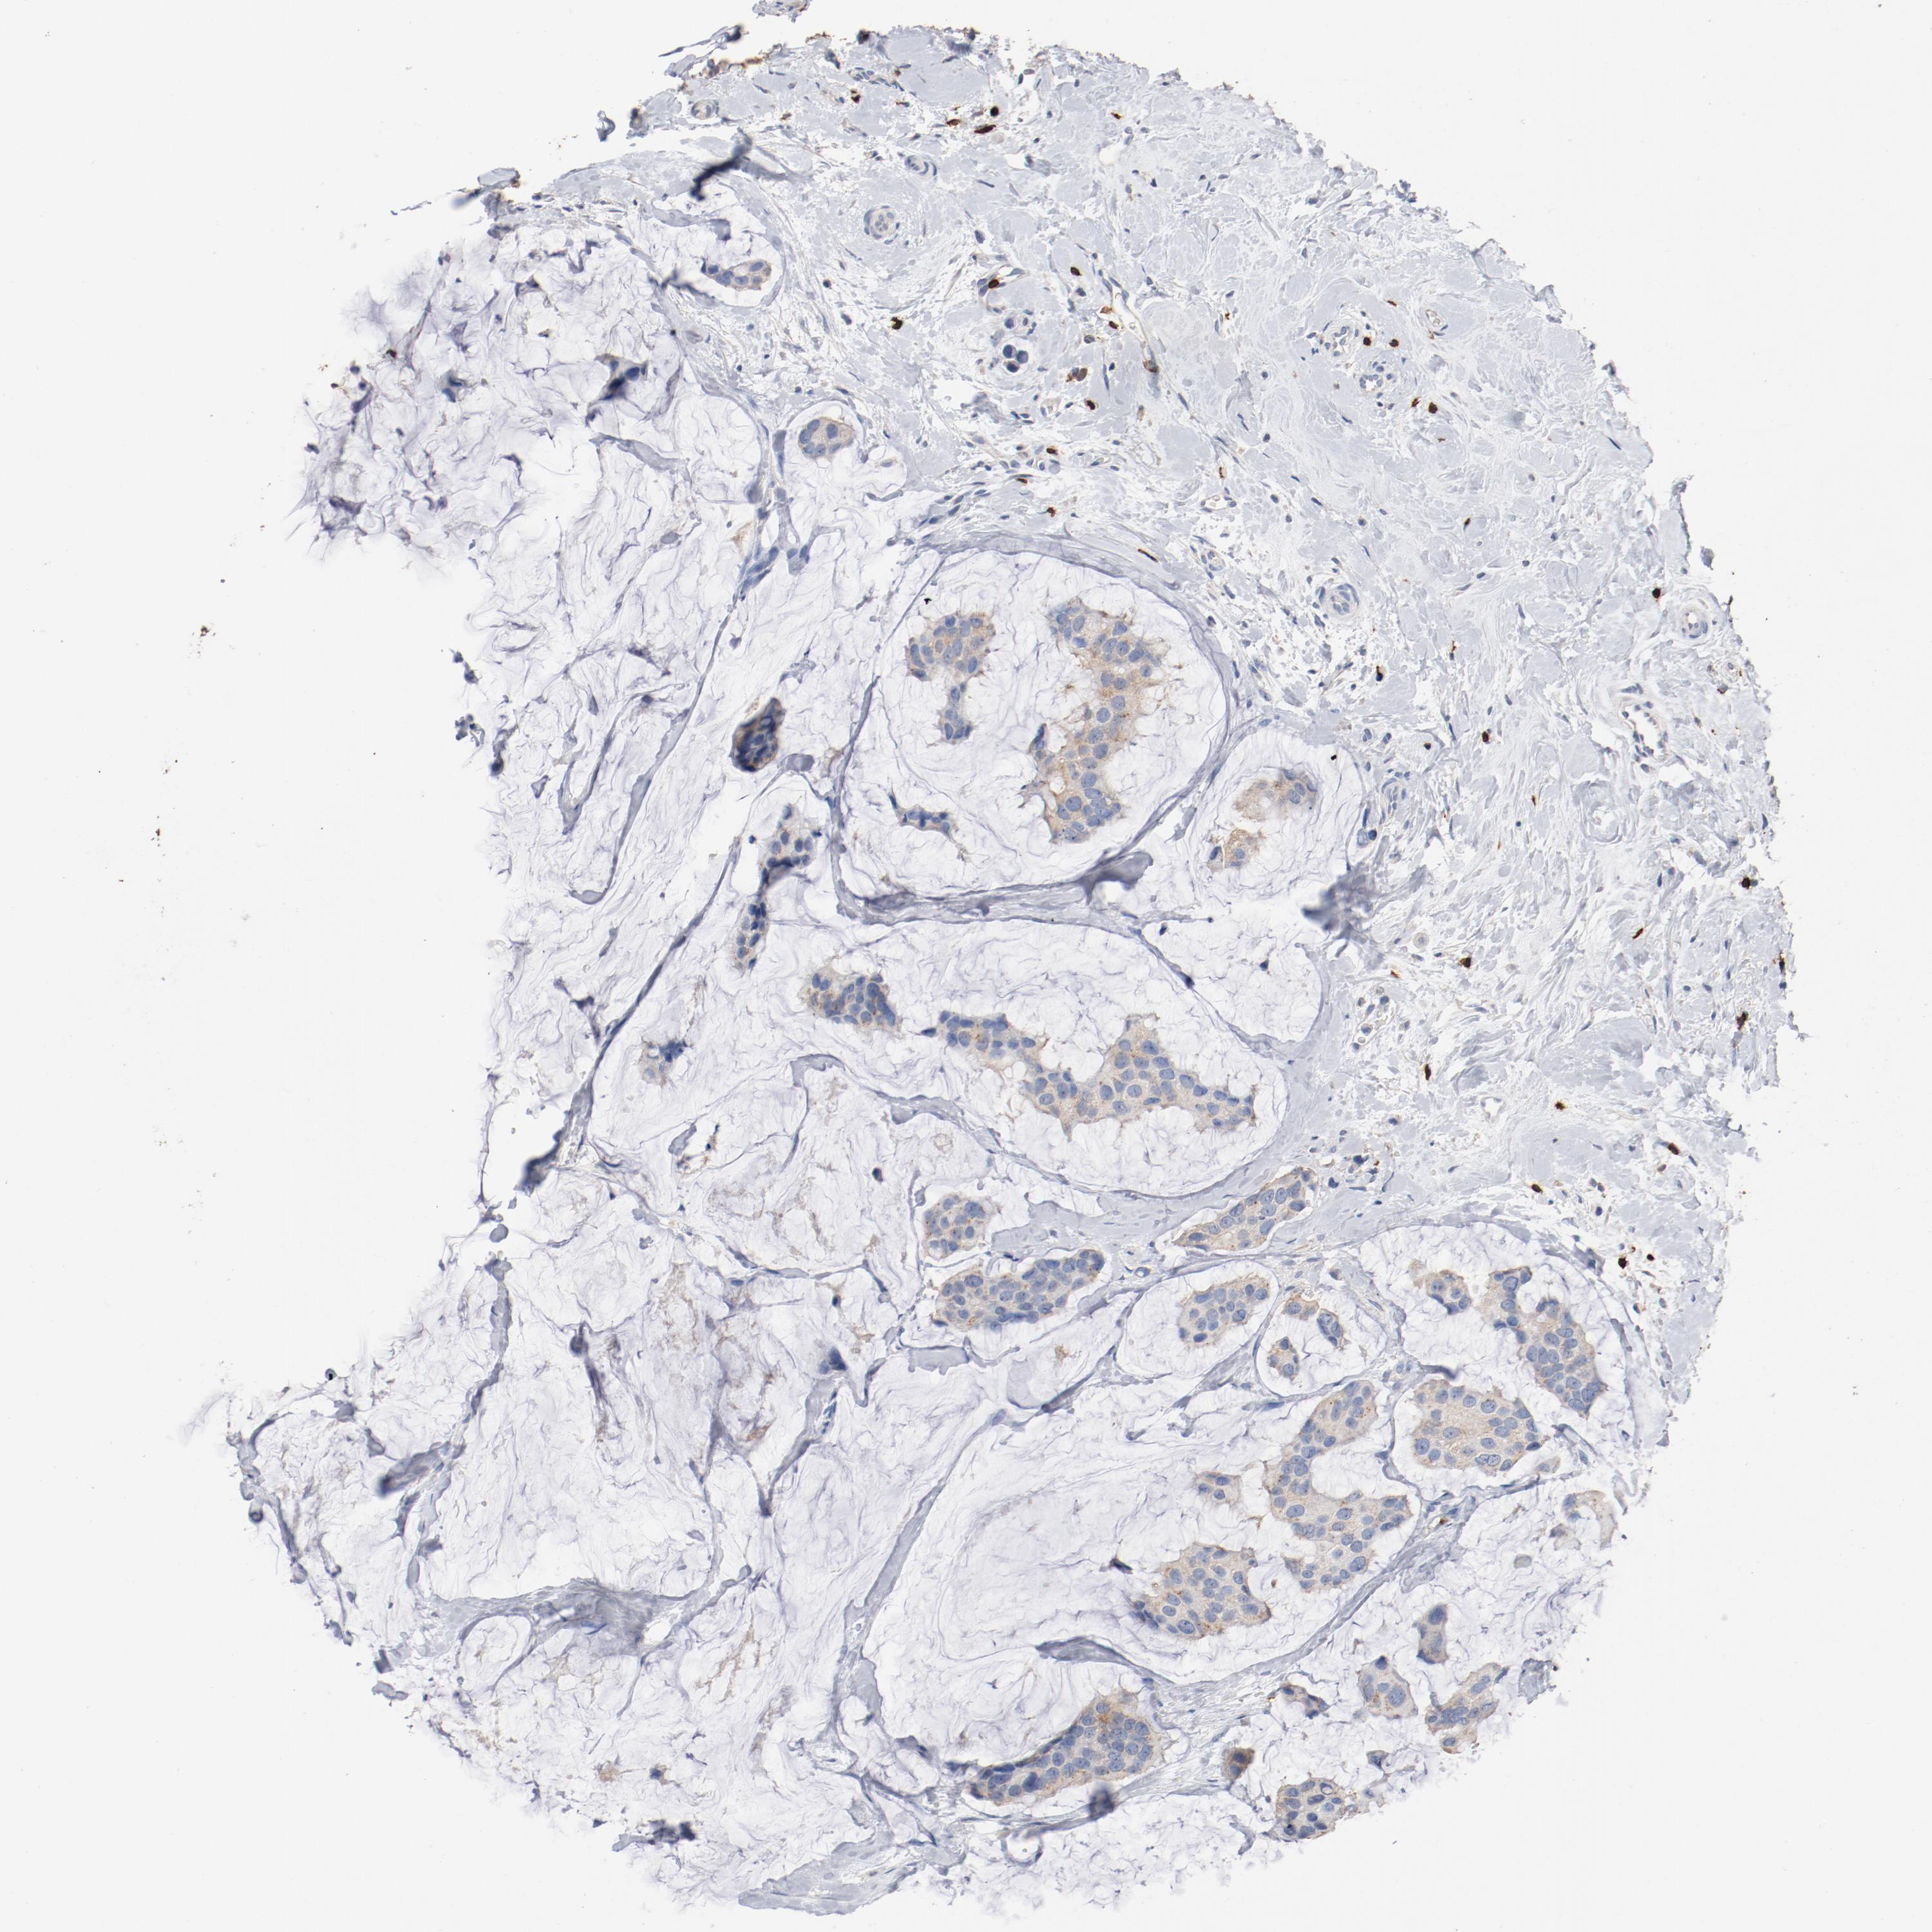

BRCA TCGA BRCA VALIDATION PROTEIN EXPRESSION

ANTIBODIES

AND

VALIDATION